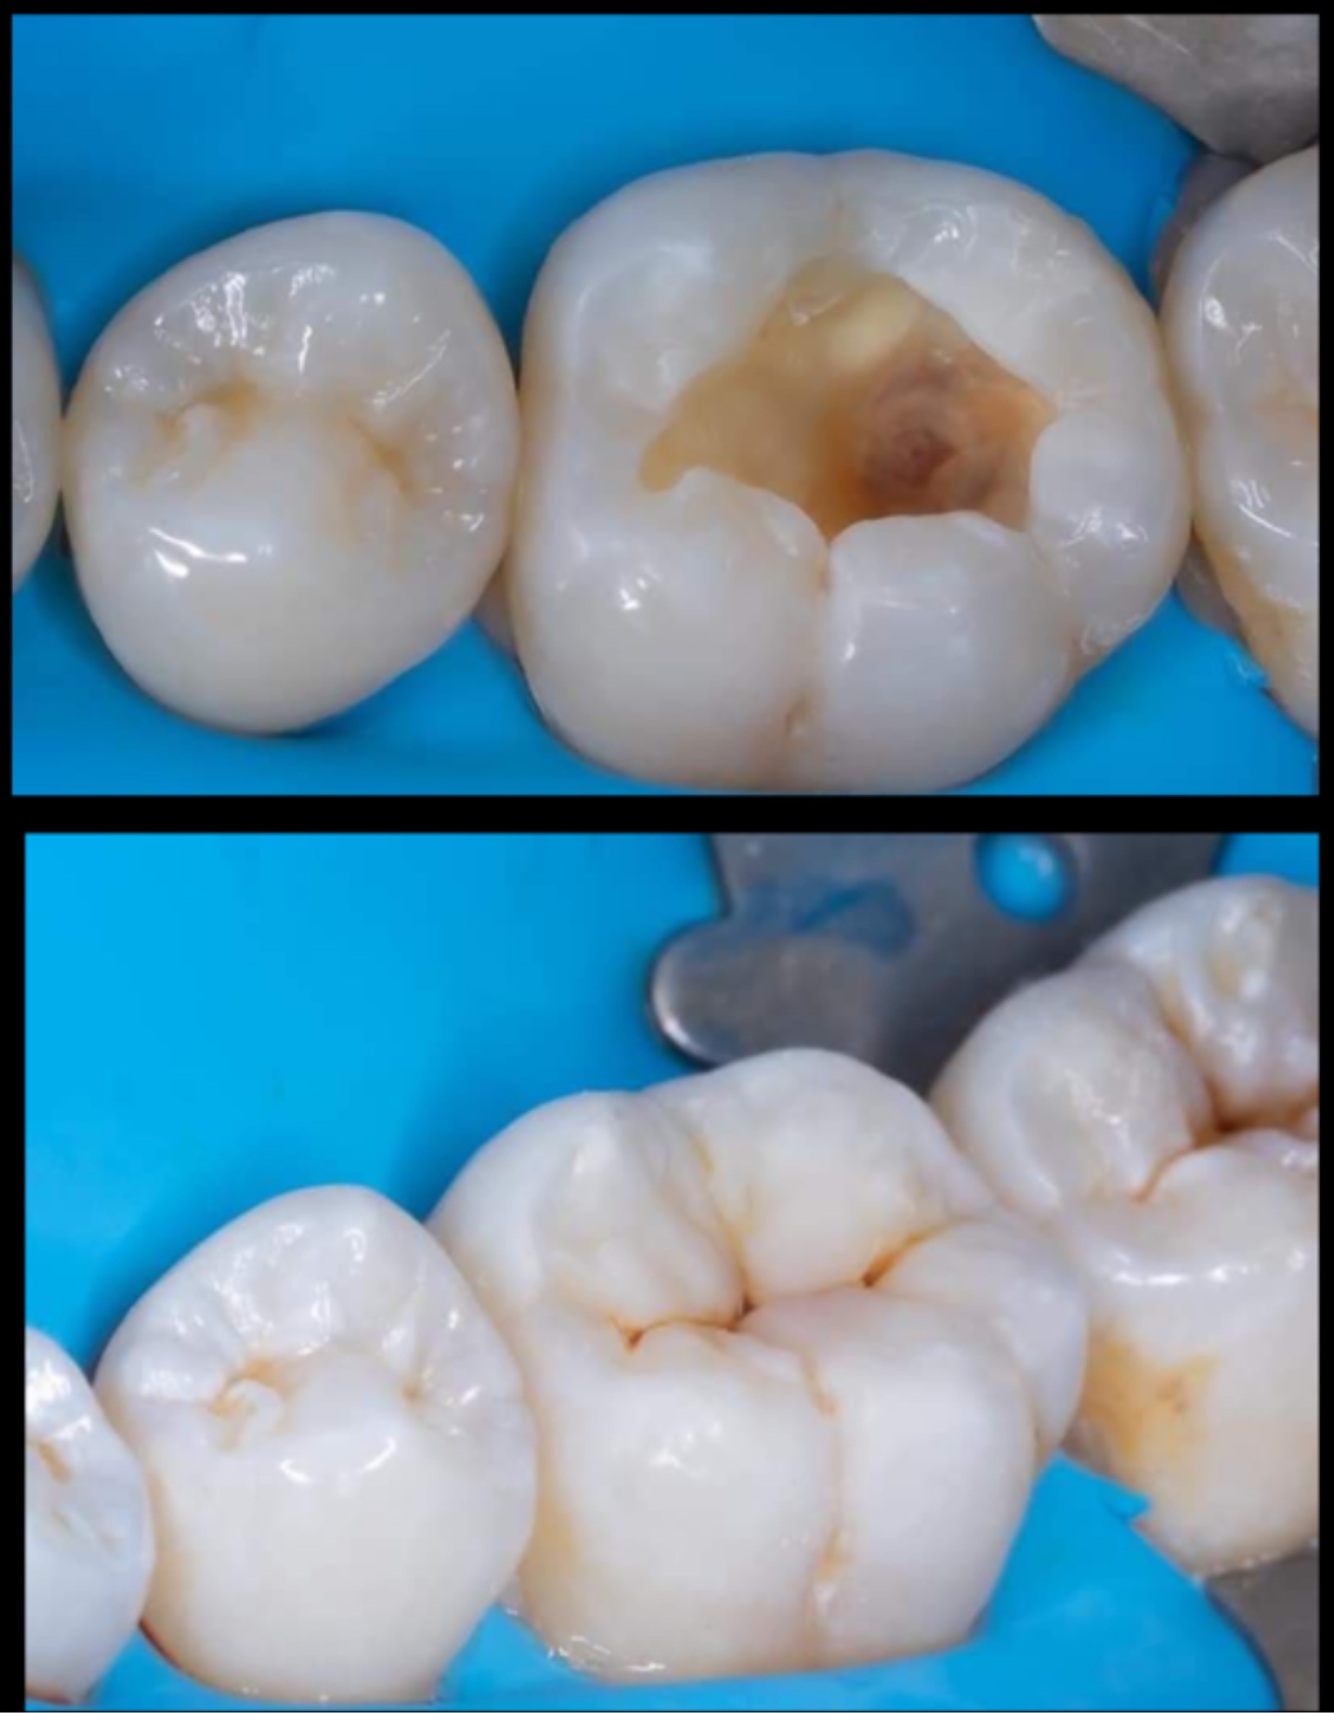

Q

Identify the restored tooth using both the long-hand and FDI notation systems:

A

Lower left first molar, 36